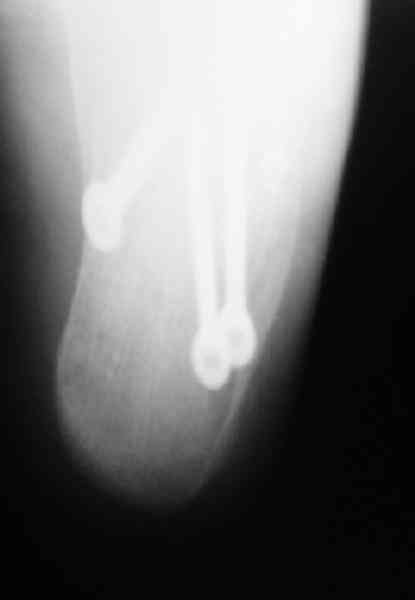

Re: Перелом пяточной кости

Пяточной пластиной